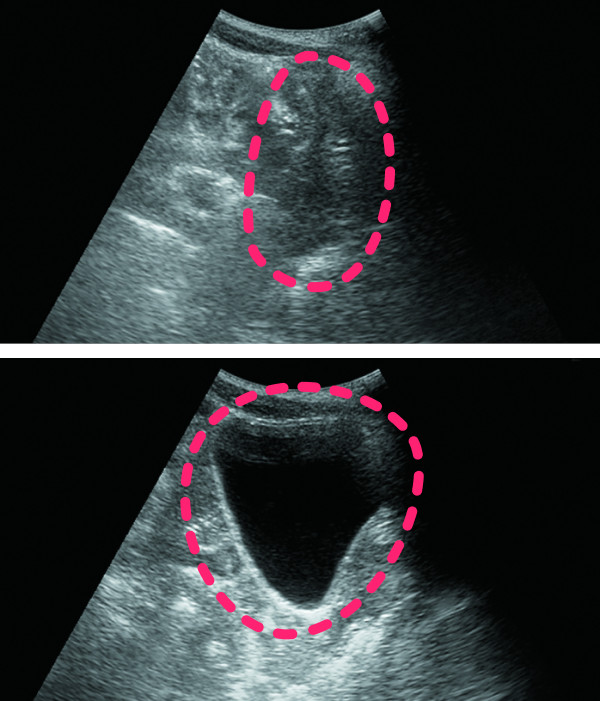

超音波診断装置でとらえた膀胱のエコー画像。上は膀胱に尿がたまっておらず収縮している状態で、下は膀胱に水分がたまり膨らんでいる状態。DFreeはこの違いを検知している

腹部に超音波センサーを貼り付けて膀胱の膨らみを読み取り、トイレのタイミングを事前に知らせてくれることがDFreeの特徴。自立排泄が困難な高齢者や障がいを抱える人をサポートする新たなウェアラブルデバイスとして期待されている。